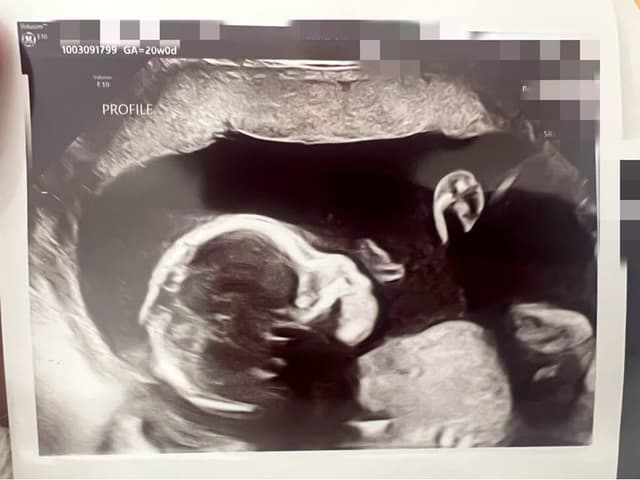

Our connection to surrogacy began with Cherry's own experience. After facing significant challenges during her first pregnancy, she welcomed her second child with the help of a Gestational Carrier. Throughout the entire process, Jane stood beside her — as a friend, a researcher, and a constant source of strength. Together, we navigated the doctors, the emotions, the uncertainties, and the incredible moments of gratitude.